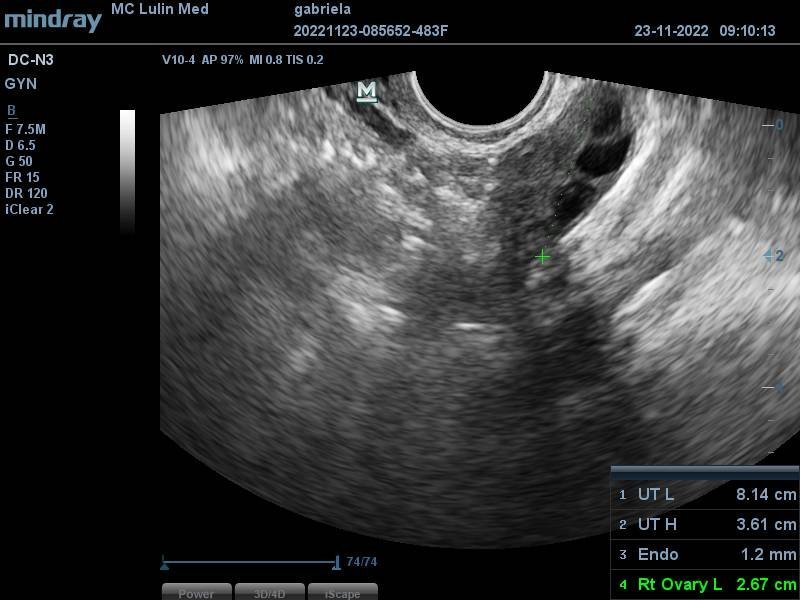

Какво представлява изображението от ехографията на 5-седмична и 2-дневна бременност?

Какво представляват черните точки в матката на ехографската снимка?